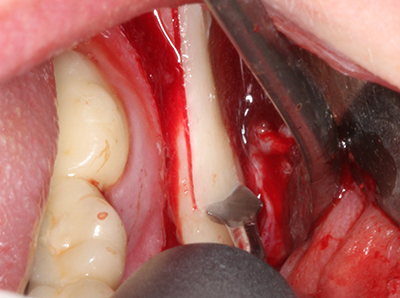

En la extracción de bloques óseos la piezocirugía también presenta ventajas adicionales: Además de la alta precisión en la osteotomía que ya se ha descrito antes, se ha comprobado que el uso de los delgados insertos de sierra resulta especialmente cuidadosas con el hueso. Frente a esto, sobre todo cuando se usan las fresas de Lindemann, cabe esperar pérdidas en la extracción significativamente más altas debido al mayor grosor de la parte frontal del cabezal (Lakshmiganthan, Gokulanathan et al. 2012). La separación basal que se necesita en particular en los injertos de bloque extraídos de forma retromolar se ve facilitada mediante sierras perpendiculares especialmente previstas a tal fin, lo que permite considerar que la cirugía piezoeléctrica es un procedimiento preciso y seguro para la obtención de bloques de hueso en el área retromolar (Happe 2007) (fig. 1-12).

Si es preciso realizar intervenciones quirúrgicas en las que el hueso está en contacto directo con estructuras sensibles, como son los vasos sanguíneos o los nervios, los instrumentos rotativos presentan un enorme potencial de provocar lesiones iatrogénicas. Así, precisamente en la representación de nervios después de una lesión iatrogénica, o en el transcurso de la lateralización de un nervio para resecciones, reconstrucciones o incorporación de implantes, los equipos piezoeléctricos pueden resultar muy útiles para preparar la tapa ósea y retirar las partes de tejido duro cercanas al nervio (fig. 17-20). Por lo general, un ligero contacto del cordón nervioso con el inserto piezoeléctrico no tiene consecuencia alguna; ahora bien, un procedimiento poco cuidadoso con movimientos tipo sierra o piezas de trabajo sobre la base ósea aún existente puede provocar lesiones nerviosas temporales o incluso permanentes. Con todo, el riesgo de sufrir una lesión de este tipo se considera significativamente inferior que en los casos en los que se utilizan sierras y fresas (Pereira, Gealh et al. 2014).